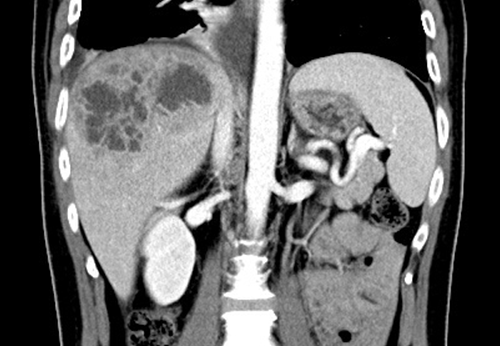

上圖:患者的影像醫學檢查可發現肝臟有嚴重膿瘍

患者入院時除高燒外,亦合併有腸胃道不適、上腹脹的臨床表現,且常規抽血檢驗呈現白血球及肝指數上升,故予以安排肝臟超音波及腹部腦斷層掃瞄,赫然發現有巨大的肝膿瘍。此外,在一系列的追蹤之下,患者的血糖值持續偏高,也符合糖尿病的臨床診斷。照會放射科醫師,緊急執行電腦斷層指引經皮穿肝膿瘍引流,並合併適當的抗生素療法、妥善的血糖控制,C先生的臨床感染症狀才逐漸控制且獲得改善。幸好立即接受適當的治療,否則很可能在數日內因肝膿瘍感染導致嚴重敗血症,進而有生命危險。